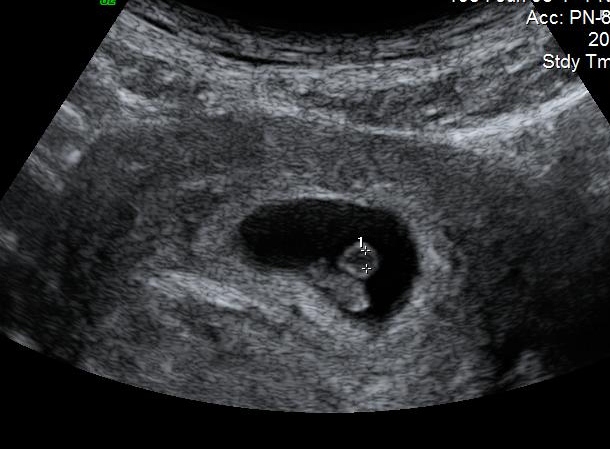

MALE- RIGHT SIDE

Attachment 2066